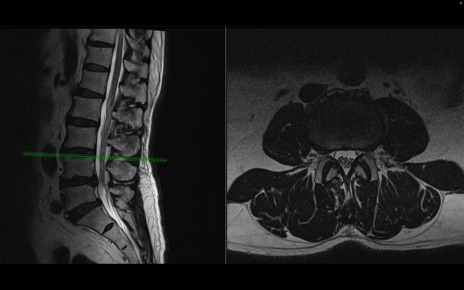

【整形】TIPS症例2 腰椎MRI 横断像と矢状断像

【症例】70歳代男性

【主訴】左下肢痛

【現病歴】2週間前くらいから腰痛、左下肢痛あり。左臀部から大腿、下腿外側のしびれが常時ある。歩行とともに同部位の痛みあり。

【身体所見】Lasegue70-/60+、Bragard-/±、PTR ±/±、ATR -/-、IP 5/5、TA 5/4、TS 5/5、EHL 右第1足趾なし/3、FHL 5/5、hypersthesia(-)、足背動脈触知良好

異常所見と診断は?